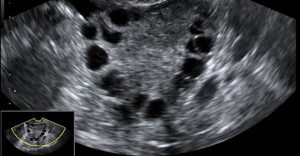

La fecundación in vitro convencional consiste en la estimulación de la maduración de los óvulos múltiple mediante el uso de medicamentos; aspiración de los ovocitos justo antes de la ovulación por vía vaginal su inseminación con los espermatozoides del esposo o donante, fuera del organismo materno. Tras la fecundación y posterior división celular, loa embriones obtenidos son transferidos al útero materno.